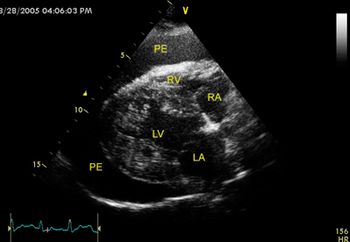

Pericardial effusion presents clinicians with a challenge when diagnosing the underlying cause, since the prognosis can be favorable in certain cases. Partial pericardectomy can be performed via thoracoscopy; and in select cases, this minimally invasive procedure can provide long-term relief of clinical signs.

Neoplastic and idiopathic pericarditis are common causes of pericardial effusion, a highly morbid condition.

A 10-year-old 35.9-lb (16.3-kg) intact female Wheaton terrier was referred to the teaching hospital at Virginia Tech for evaluation of dyspnea.